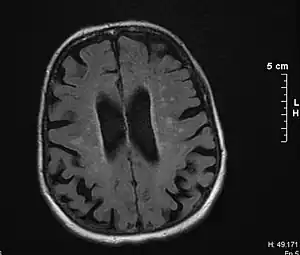

![]() | |

| Brain atrophy on MRI from vascular dementia | |